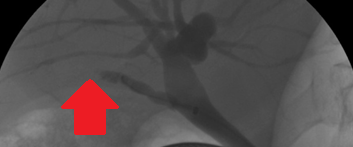

Percutaneous transhepatic cholangiography. Cystic dilatation of intrahepatic biliary duct with mucinous content (Courtesy Dr. V. Penopoulos)